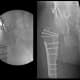

Although Mr. J’s intra-articular causes of FAI were optimized, the extra-articular rotational deformity of the femur did not allow for adequate impingement-free range of motion. Therefore, a subtrochanteric derotational osteotomy with internal fixation was performed to bring the femur into normal rotational alignment. Bone autograft harvested from the greater trochanteric bed was used to supplement the osteotomy fixation (Fig. 2).